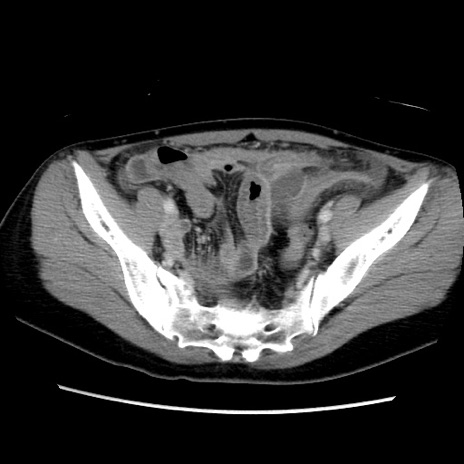

症例39(横断像)

【症例】40歳代女性

【主訴】上下腹部痛

【現病歴】2日目から下腹部痛あり。夜間は痛みで眠れなかった。昨日より上腹部痛と下痢が出現。臥位で痛みは軽快したため、休んでいた。本日になって臥位でも立位でも痛みが強くなってきたため救急要請。

【既往歴】子宮内膜症

【身体所見】部:平坦・軟、左上下腹部に圧痛あり、反跳痛あり。

【データ】WBC 21800、CRP 26.78